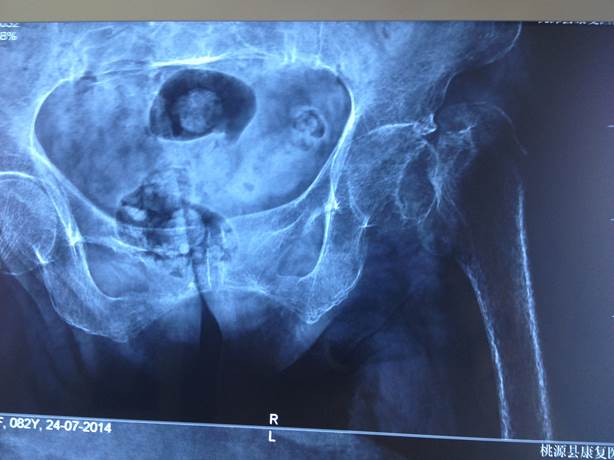

入院诊断:左侧股骨头坏死 。

入院查体:轮椅入院,双髋关节活动受限,左髋关节广泛压痛,左侧臀部深压痛,髋关节外侧大粗隆、臀中肌叩击痛,左下肢外展外旋,内旋活动受限。Thomas征(+)Allis征(+);左侧股四头肌轻度萎缩。

治疗经过:于2014.7.29 10:30-11:55在联合腰麻麻醉下行了左侧半髋置换术(水泥型)。